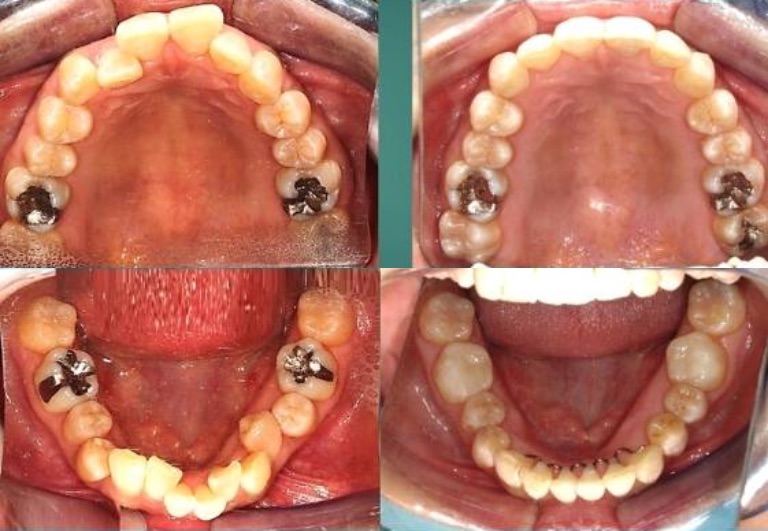

同クリニックでは、成人後の歯列矯正において気をつけるべき歯根や歯槽骨の状態も、最新機器と技術を駆使して精確に確認し、治療前・治療中・治療後の口腔内も撮影していきます。歯の健康状態を精確に検診し、親身なコンサルテーションを実施し、口内の状態と理想の歯並びと顔の輪郭を把握し、その上で一人一人のライフスタイルに合わせた治療プランを提供できる経験豊富な歯科医が、キム歯科医院長です。